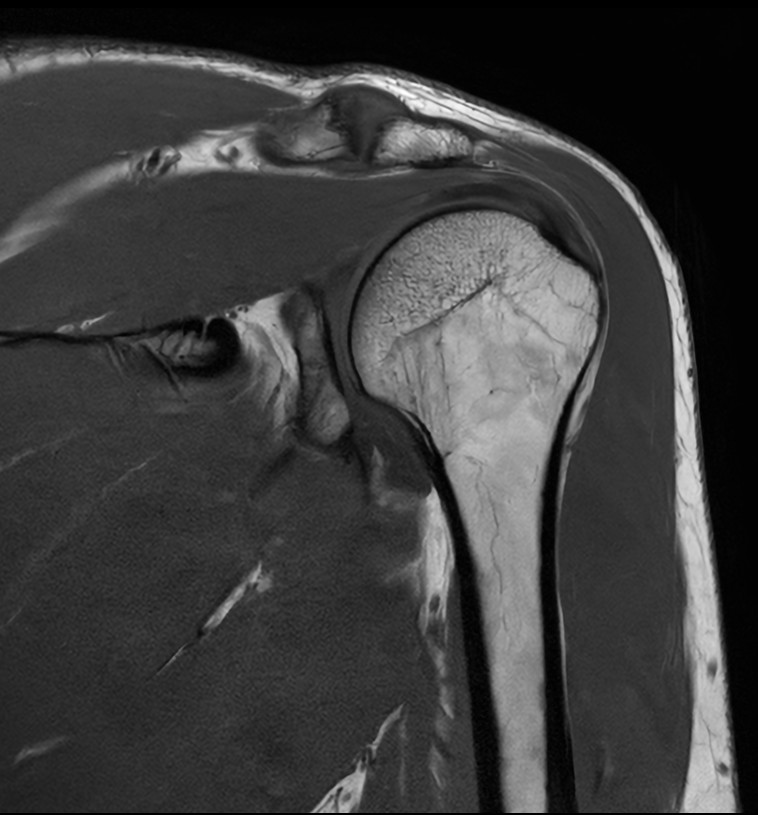

High quality Shoulder imaging with SmartSpeed Precise